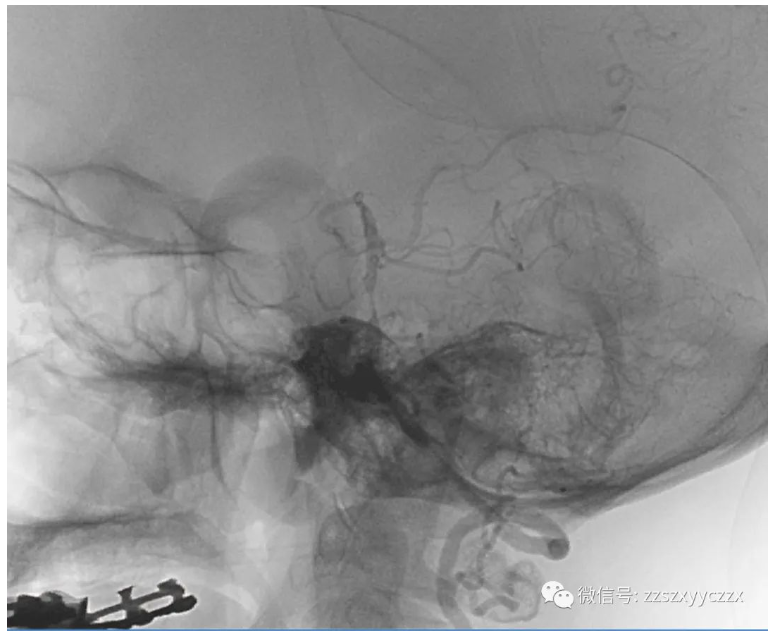

3、DSA:右侧椎动脉起始处闭塞;左侧椎动脉起始处重度狭窄,狭窄率为75%,基底动脉下段轻度狭窄,狭窄率约30%,基底动脉中段重度狭窄,狭窄率约85%,左侧大脑后动脉P1段缺如,右侧大脑后动脉显影可;血管内可见多发斑块形成。

左侧椎动脉起始处药物球囊扩张术前后。